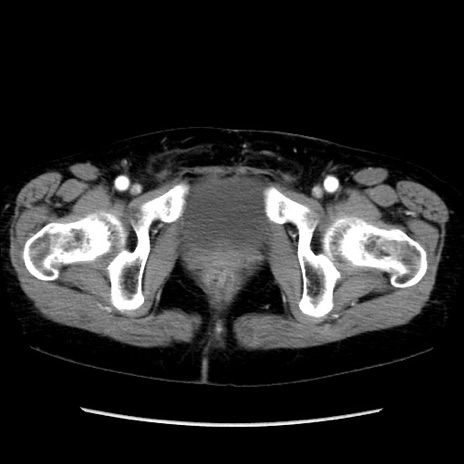

症例32(横断像)

【症例】40歳代 女性

【主訴】上腹部痛、嘔気・嘔吐

【現病歴】約9時間前頃から急に上腹部痛、嘔気、嘔吐が出現。改善しないため救急要請。

【既往歴】子宮頚癌(広汎子宮全摘術、放射線療法)、腸閉塞

【身体所見】腹部:平坦、軟、腸雑音亢進、上腹部を中心に腹部全体に圧痛あり。

【データ】WBC 8400、CRP 0.03